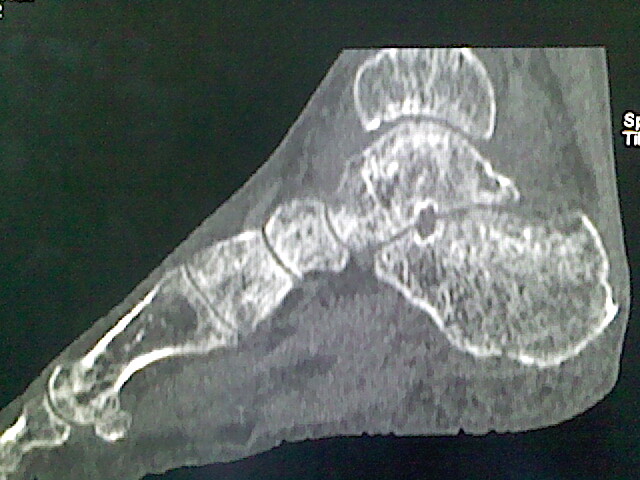

男,76岁,左小腿疼痛,不能站立

本例骨质改变主要表现为滑膜或韧带区的骨侵蚀融解(胫腓联合区骨质破坏无硬化边),距骨后部骨质破坏区有硬化边及死骨样改变.所以,本例考虑关节结核可能性大,绒毛膜结节性滑膜炎多发于中年,且极少见于膝髋以外的关节,骨质硬坏也以压陷吸收为主,有明显的硬化边,骨膜增生呈结节状(可以mr鉴别),所以本例暂除外.

另不除外可引起相似表现的其他炎症如布氏杆菌性关节炎等